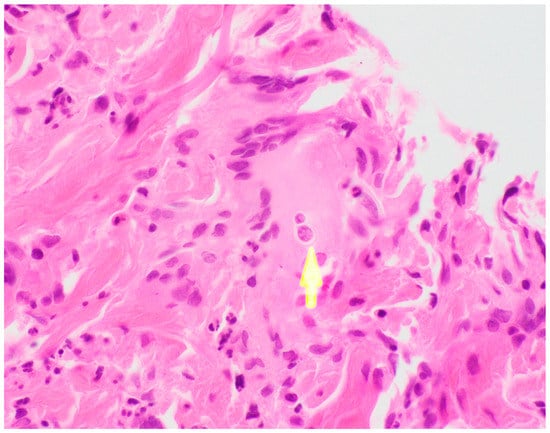

Ultimately, a punch biopsy of his left second metacarpophalangeal joint was taken in addition to cultures from the left hip sinus tract drainage which revealed the presence and growth of Blastomyces dermatitidis after 12 days of hospitalization, respectively (Figure 4 and Figure 5). Serology testing was also ordered, which was positive for Blastomyces antibody immunodiffusion (ID), though negative for Blastomyces antibody complement fixation (CF). Notably, a urine histoplasma antigen test was positive with a result of >25.0 ng/mL with a negative histoplasma antibody ID test, likely indicating a component of cross-reactivity in the presence of Blastomyces dermatitidis.

Figure 5. Left 2nd MCP biopsy, H&E stain demonstrating characteristic broad-based budding seen in Blastomyces infections.